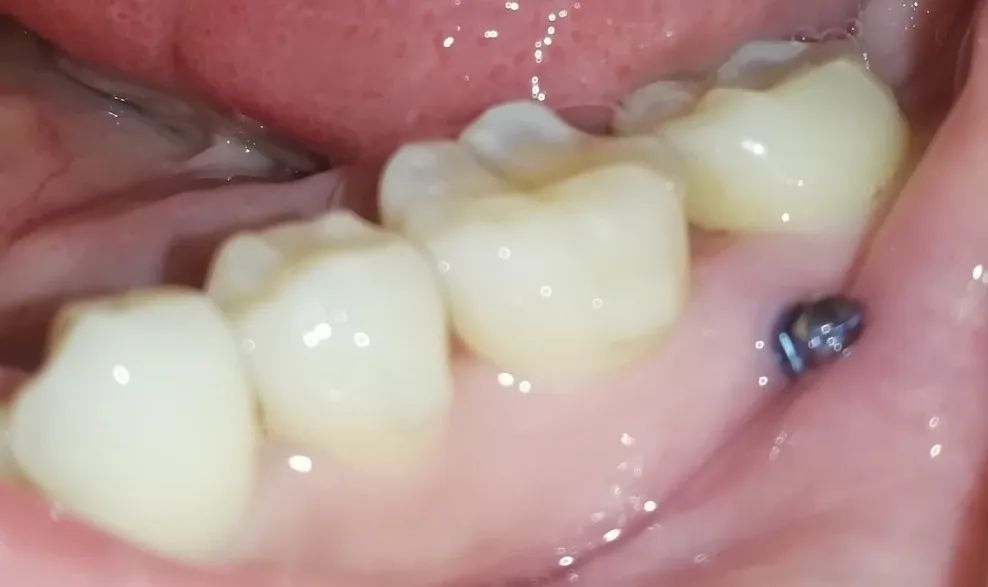

可以大致看看牙釘?shù)奈恢?/p>